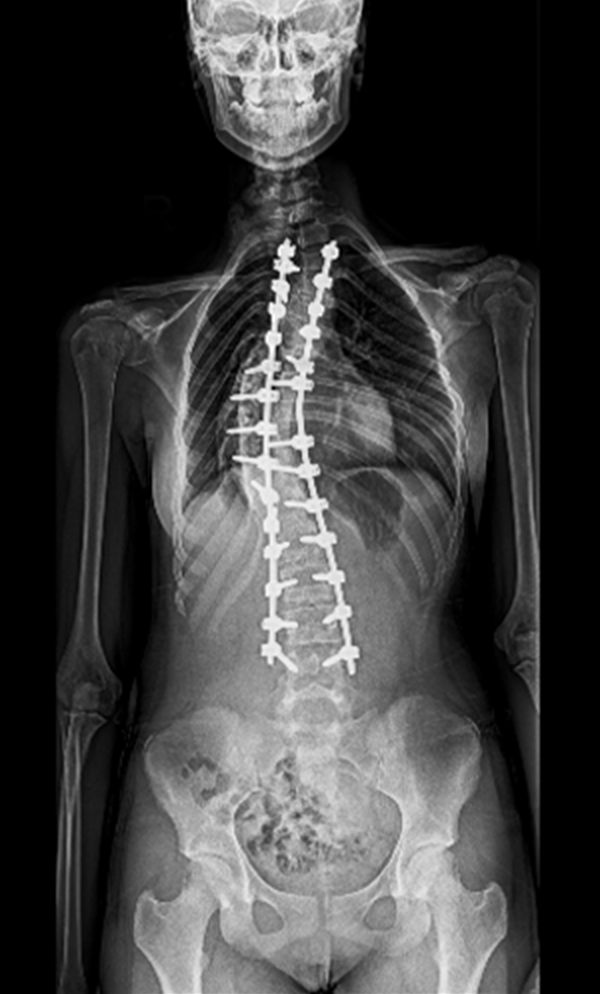

BEYOND RECOVERY : REAL STORIES

Gallery : Before - After